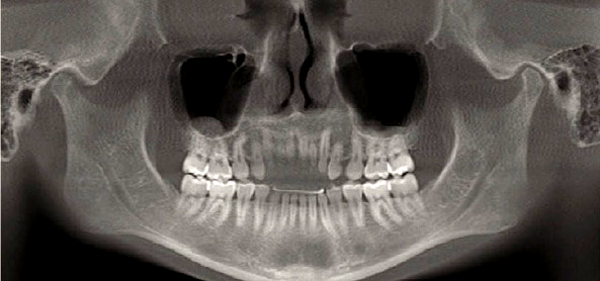

A screening image, typically a panoramic radiograph, permits assessment of the form of the condyle and the integrity of the cortex and is an important adjunct to the initial history and examination. An additional benefit of a panoramic image is the ability to visualize other structures in the maxillofacial region. In a panoramic image the condyles are intentionally brought down and forward in the fossae by having the patient protrude the mandible, but the condyles may still be partially obscured by adjacent bony structures.

With the advent of cone beam CT (CBCT) imaging, it is now possible to acquire a panoramic image with the teeth together, thus making it possible to see the condyles in their relationship to their fossae.

Because conventional panoramic imaging is still more common still more commonly available in dental offices than is CBCT, and because a conventional panoramic exposes the patient to less radiation than a CBCT scan, the conventional panoramic is the preferred choice as a screening image for most TMD patients.